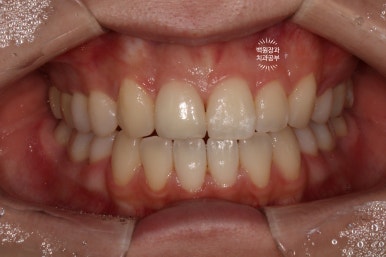

Before & After

치아미백과 잇몸성형술 그리고 단 한개의 지르코니아 크라운을 통해 얻은 심미적인 결과입니다!

치아는 보다 밝아졌고, 앞니는 더 나란히 - 가지런해진 모습이 훨씬 보기 좋아졌네요 :)

밝은 색상의 앞니는 밝은 인상을 가지는데 큰 역할을 합니다.

잇몸 높이를 맞춰드리기 위해 잇몸 성형술 (치은 성형술)을 시행했는데요, 좌우 대칭의 잇몸높이를 갖기 위해 생각보다 경험있는 치주과 전문의의 진료가 필요합니다. 위에서 보시는 Before & After 처럼 거의 완벽에 가까운 잇몸 형태를 재현해낼 수 있습니다!

단 한개의 앞니만을 수정함으로써 생각보다 만족스러운 결과를 이끌어낼 수 있어서 기억에 남는 환자분입니다.

심지어 지르코니아 크라운으로 치료받았던 치아는 원래 작았던 측절치였기에 치아 삭제량도 최소로 할 수 있었습니다!! 상당히 뿌듯하고 자랑할만한 결과였고, 한편으로 일련의 치료를 잘 따라와주신 환자분께 감사의 말씀을 전하고 싶습니다.